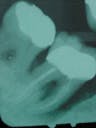

In 1997, the radiograph showed something amazing - the formation of new bone in the furcation and at the base of the pocket. Never in our wildest dreams did we expect to see this!

In 1998, the radiograph showed the area to be stable.

1997

1998